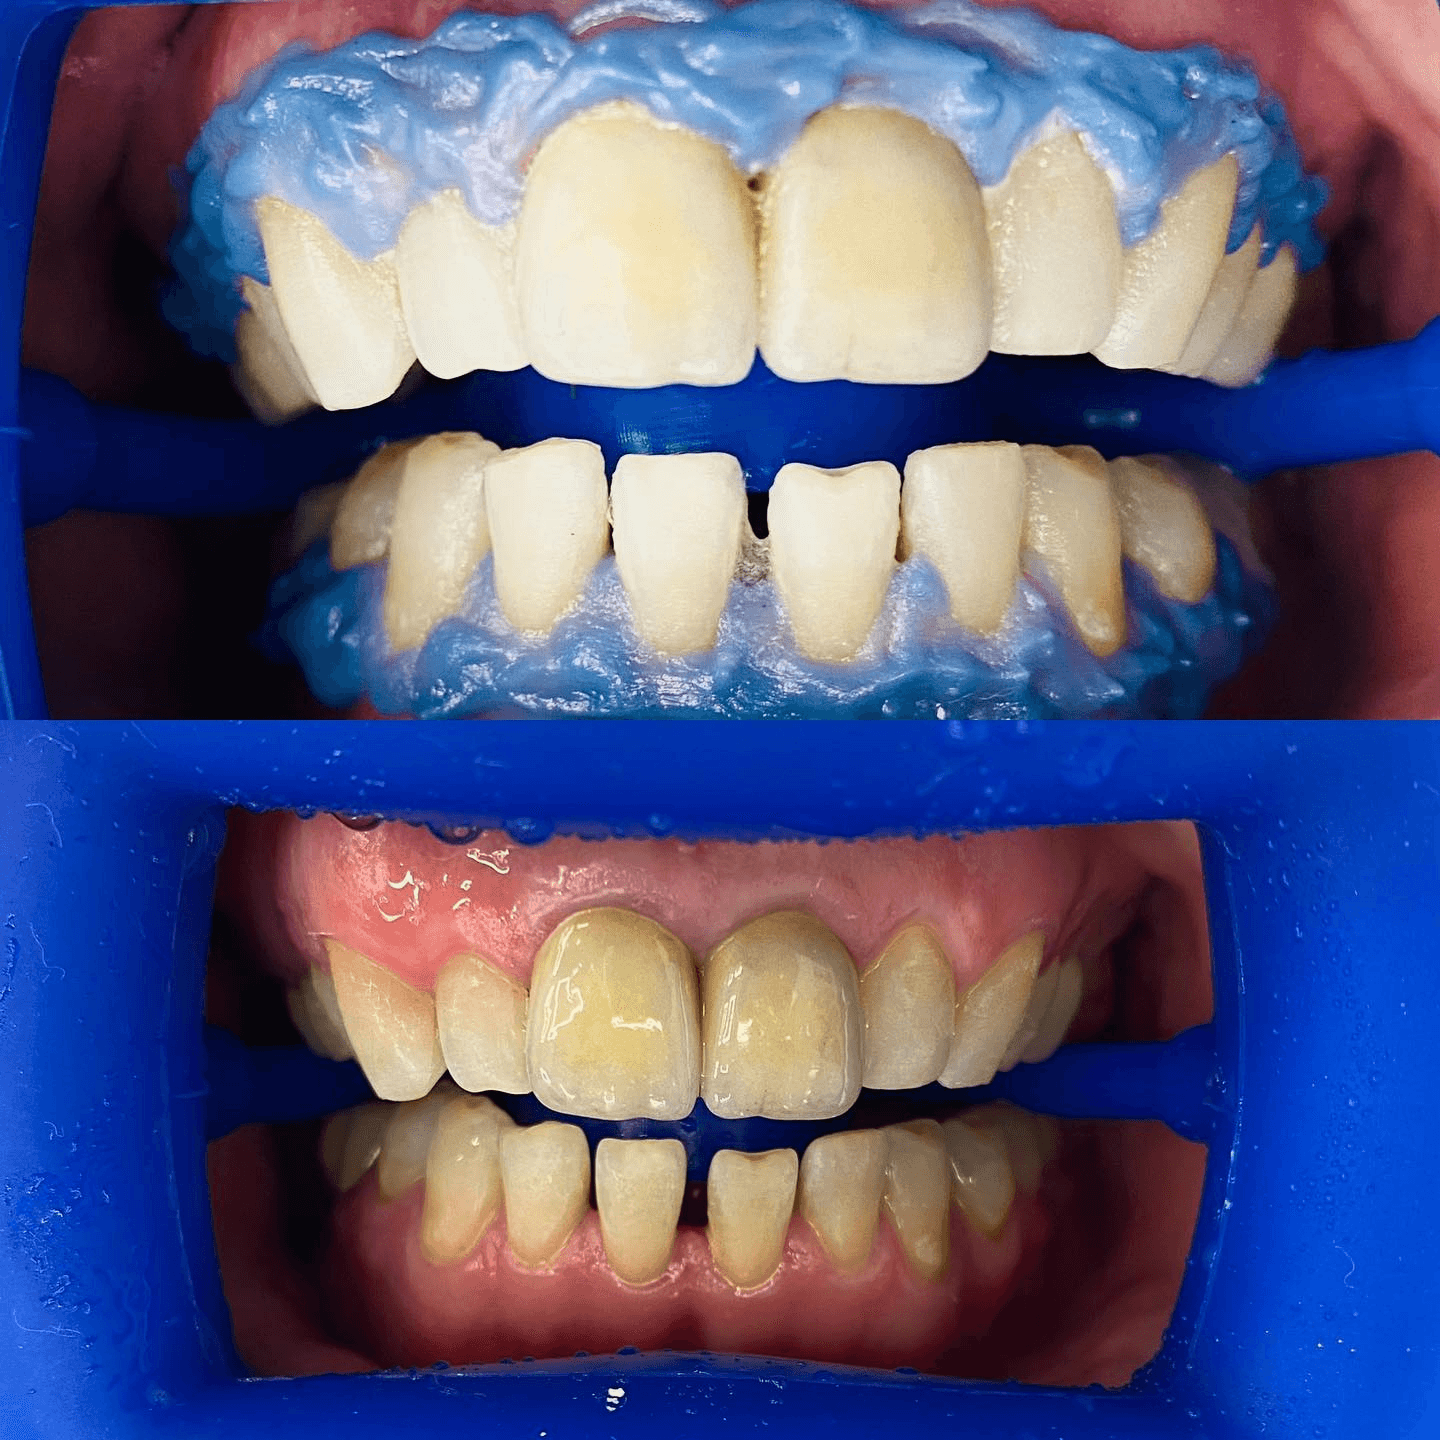

תוצאות - בהסכמה ובטעם טוב

צילומים מהמרפאה - מוצגים בהתאם להסכמות מטופלים ולכללי הפרסום.

חשוב: יש להציג תמונות לפני/אחרי רק בהסכמת מטופלים ובהתאם לכללי הפרסום הרפואי.

צילומים מהמרפאה - מוצגים בהתאם להסכמות מטופלים ולכללי הפרסום.

חשוב: יש להציג תמונות לפני/אחרי רק בהסכמת מטופלים ובהתאם לכללי הפרסום הרפואי.